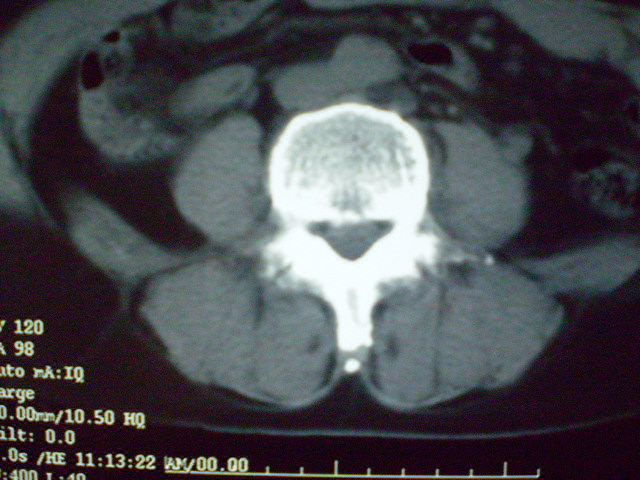

f 60y,b超提示脂肪瘤.[img][/img]

右侧附件囊性畸胎瘤,三种组织均见.

右侧附件囊性畸胎瘤.

那个高密度灶形状好象牙齿。典型,收藏了

脂肪密度肿块,内可见团块状影,典型皮样囊肿

的确比较典型的畸胎瘤!不过,应该确切的说是盆腔畸胎瘤,右侧附件来源的可能性比较大。

有钙化,畸胎瘤